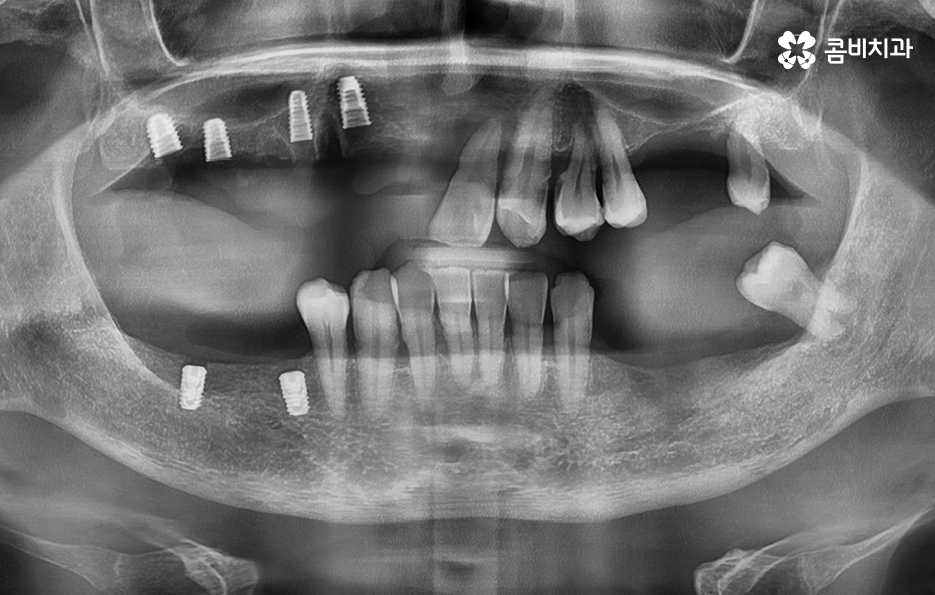

노년기에 치아 상실이 증가하는 큰 원인은 치주염의 장기적 누적 효과로서 치주염은 잇몸 염증이 잇몸뼈까지 파고들어 뼈를 녹여 치아를 지탱하지 못하게 만드는 병으로 젊을 때는 잇몸이 어느 정도 회복되기 때문에 크게 느껴지지 않지만, 나이가 들수록 회복 속도는 느려지고 염증은 더 빨리 확산되며 잇몸뼈가 한 번 녹기 시작하면 다시 원래 그대로 회복되는 것은 사실상 어렵기 때문에 치아는 점점 흔들리고, 결국 발치까지 이어질 수 있어요

노년기 환자분들의 상당수는 갑자기 치아가 흔들리기 시작했다고 이야기하지만 실제로는 오랜 기간 진행된 치주염이 임계점에 도달한 결과로서 치주염은 조용히 진행되기 때문에 정기 검진이 없으면 치아 상실까지 이어지는 경우가 많이 나타나고 있었어요

다만 여기서 주의해야 할 점은 65세이상 임플란트 개수 평생 2개까지 혜택을 받을 수 있다는 점에서 되도록 자연치아의 건강을 잘 유지하면서 필요한 시점에 혜택을 잘 활용하는 것이 중요하겠고 노년기에 치료를 받아야 한다는 점에서는 잇몸 뼈의 상태 및 전신건강까지 잘 고려할 수 있는 시스템이 잘 갖춰지고 경험 많은 치과의사와 함께 치료 계획을 잘 세워야 하며 건강보험 혜택에서는 뼈이식이나 상악동거상술, 보철물의 변경 같은 추가적인 사항에 대해서는 별도의 비용으로서 치료비를 납부해야 하므로 각 환자분들에게 적합한 치료 계획에 대해 잘 이해하여 치료비 예산을 잘 계획하실 필요가 있었어요.